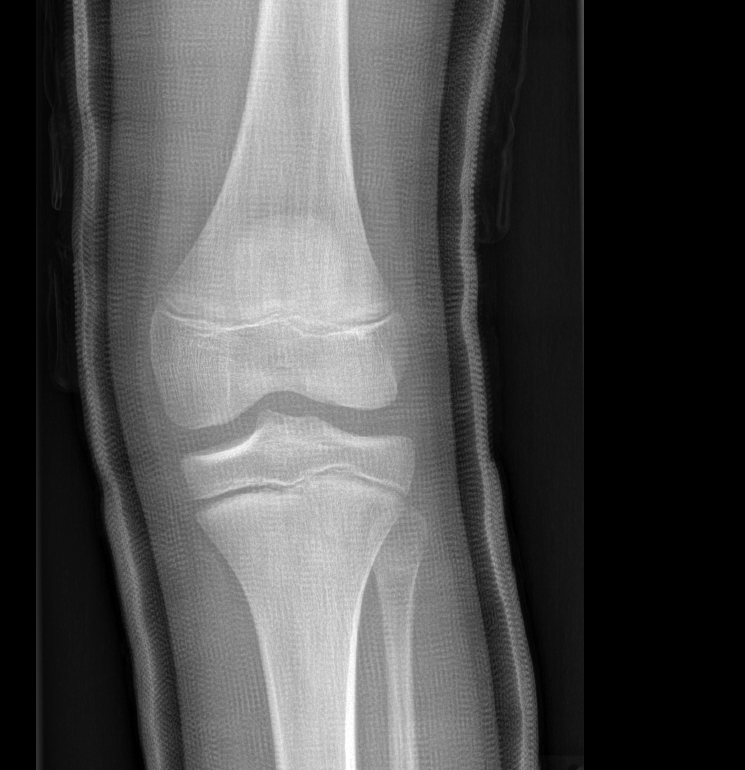

Info Images Findings Impression Reco/Acuity Case Images View Images / Launch Visage Case Notes History 2-month-old presents with decreased right arm movement, increased fussiness, and increased sleepiness for 2 days. Suspected non-accidental trauma. Exam Skeletal survey Prior Study none Dicom View Reference Material

Section 1 Submit Findings CB1550 Findings Skeletal Survey - Technique Check Skull AP/Lat Yes No Cervical and Thoracolumbar spine Yes No Chest X-Ray Yes No Ribs – Left/Right Oblique Yes No Abdominal X-Ray Yes No Pelvis with both hips Yes No Bilateral Humerus, Forearm, Hand Yes No Bilateral Femur, Tibia/fibula, feet Yes No Any additional lateral views of the extremities Yes No The exam is over or under penetrated. Yes No The exam may or may not be limited by overlying structures or soft tissues, body habitus, patient positioning, support devices, or motion. Yes No The area of concern is indicated by the patient, technologist, or care provider. Yes No The area of concern is included on the exam. Yes No Soft Tissues There is soft tissue swelling, indistinctness of fat/muscle planes, gas, or laceration in the area of clinical concern. Yes No There is an effusion, fat pad displacement, or fat fluid level. Yes No There is a radiodense or lucent foreign body. Yes No There are other densities, calcifications, post-surgical changes, or support devices in the soft tissues. Yes No Any support lines/tubes. Yes No Bone There is a break or interruption of the continuity of the cortical or cancellous bone. Yes No There is overriding of the trabeculae with apparent sclerosis. Yes No There is displacement of a fracture fragment. Yes No There is bowing of the bone in addition to the fracture at the apex of the bowed bone concerning for the greenstick. Yes No There is a spiral fracture of the leg concerning for toddler’s fracture. Yes No There is abnormal angulation or bulging of the cortical surface relative to the normal cortex which could be from a buckle or torus fracture. Yes No There is a displaced fragment which may be from avulsion by a tendon, ligament, or joint capsule or from a comminuted or other fracture. Yes No The stress trabeculae or other trabeculae of the cancellous bone are interrupted or otherwise abnormal. Yes No There is subperiosteal or endosteal reaction which could indicate a healing or subacute fracture or other abnormality. Yes No There is hard/soft callus formation. Yes No There is remodeling of the bone. Yes No There is a corner fracture or metaphyseal lesion that could be from nonaccidental trauma. Yes No There are multiple fractures of different ages. Yes No There are vertebral body/spinous process fractures. Yes No There are rib fractures. Location - posterior or lateral. Yes No There is scapular/sternal fracture. Yes No There are fractures of the digits. Yes No There are wormian bones. Yes No There are intrasutural bones. Yes No There is metaphyseal abnormality (lucencies, increased density, erosion) which may be from something other than injury such as stress, metabolic disease (e.g. rickets with loss or distortion of the zone of the provisional calcification), neoplasm (e.g. leukemia), heavy metals, inflammation, or infection. Yes No There are metaphyseal spurs. Yes No There are bony deformities involving multiple bones. Yes No The bones are gracile. Yes No There are non-healing fractures. Yes No There is/are focal or multifocal lytic/lucent, blastic/sclerotic or mixed density lesion(s) or other abnormality. Yes No Overall bone density is increased or decreased with or without thinning or thickening of the cortical or cancellous bone. Yes No Growth plates, ossification centers, apophyses The growth plate(s) is/are abnormal. Yes No There is widening of the physis from a fracture with or without displacement of the epiphysis (Salter-Harris I). Yes No There is a fracture through the physis which then extends into the metaphysis with or without angulation or displacement (S-H II). Yes No There is a fracture through the physis which then extends into the epiphysis and is intra-articular, with or without angulation or displacement (S-H III). Yes No There is a fracture through the metaphysis, physis, and epiphysis which extends into the joint space with or without angulation or displacement (S-H IV). Yes No There is narrowing of the physis from a compression fracture (S-H V). Yes No The apophysis, epicondyle, secondary ossification center, or accessory ossicle is displaced or otherwise abnormal. Yes No The ossification centers are underdeveloped. Yes No Joints and alignment There is an effusion, fat pad displacement, or fat fluid level. Yes No The epiphysis or subchondral bone is fractured, interrupted, flattened, compressed, impacted, displaced, or otherwise abnormal. Yes No There is an intra-articular loose body or chondrocalcinosis. Yes No The joint is widened, narrowed, dislocated, malaligned, or incongruent. Yes No There is pseudoarthrosis. Yes No Other findings There are developmental changes or other anatomic variants or other existing conditions that may or may not be contributing to symptoms which can or should be further evaluated non-emergently or are otherwise incidental. Yes No The remainder of the exam is abnormal for age. Yes No The lungs show focal airspace opacity. Yes No There is pneumothorax. Yes No There is organomegaly. Yes No There is intra-abdominal calcification. Yes No There is displacement of the bowel loops. Yes No There is free intraperitoneal air. Yes No The bowel loops are dilated/obstructed. Yes No There is paraspinal soft tissue abnormality. Yes No